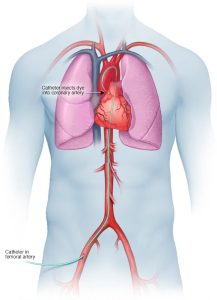

A coronary angiogram is part of a general group of heart tests and treatments called cardiac catheterization. Cardiac catheterization uses one or more thin, flexible tubes, called catheters. The tubes are placed within the major blood vessels of the body and the heart. The test requires a small cut in the skin. During a coronary angiogram, a treatment called angioplasty and stenting can be done to open any blocked arteries.

The doctor makes a small cut, called an incision, to reach an artery. This cut may be made in the leg or wrist. A thin, flexible tube called a catheter is placed in the artery and guided to the heart. You shouldn’t feel it moving through your body.

Once the catheter is in the correct position, dye flows through the tube into the heart’s blood vessels. X-ray images are taken to see how the dye moves. These images are called angiograms. If the dye doesn’t move through a blood vessel, it could mean the area is blocked or narrowed.